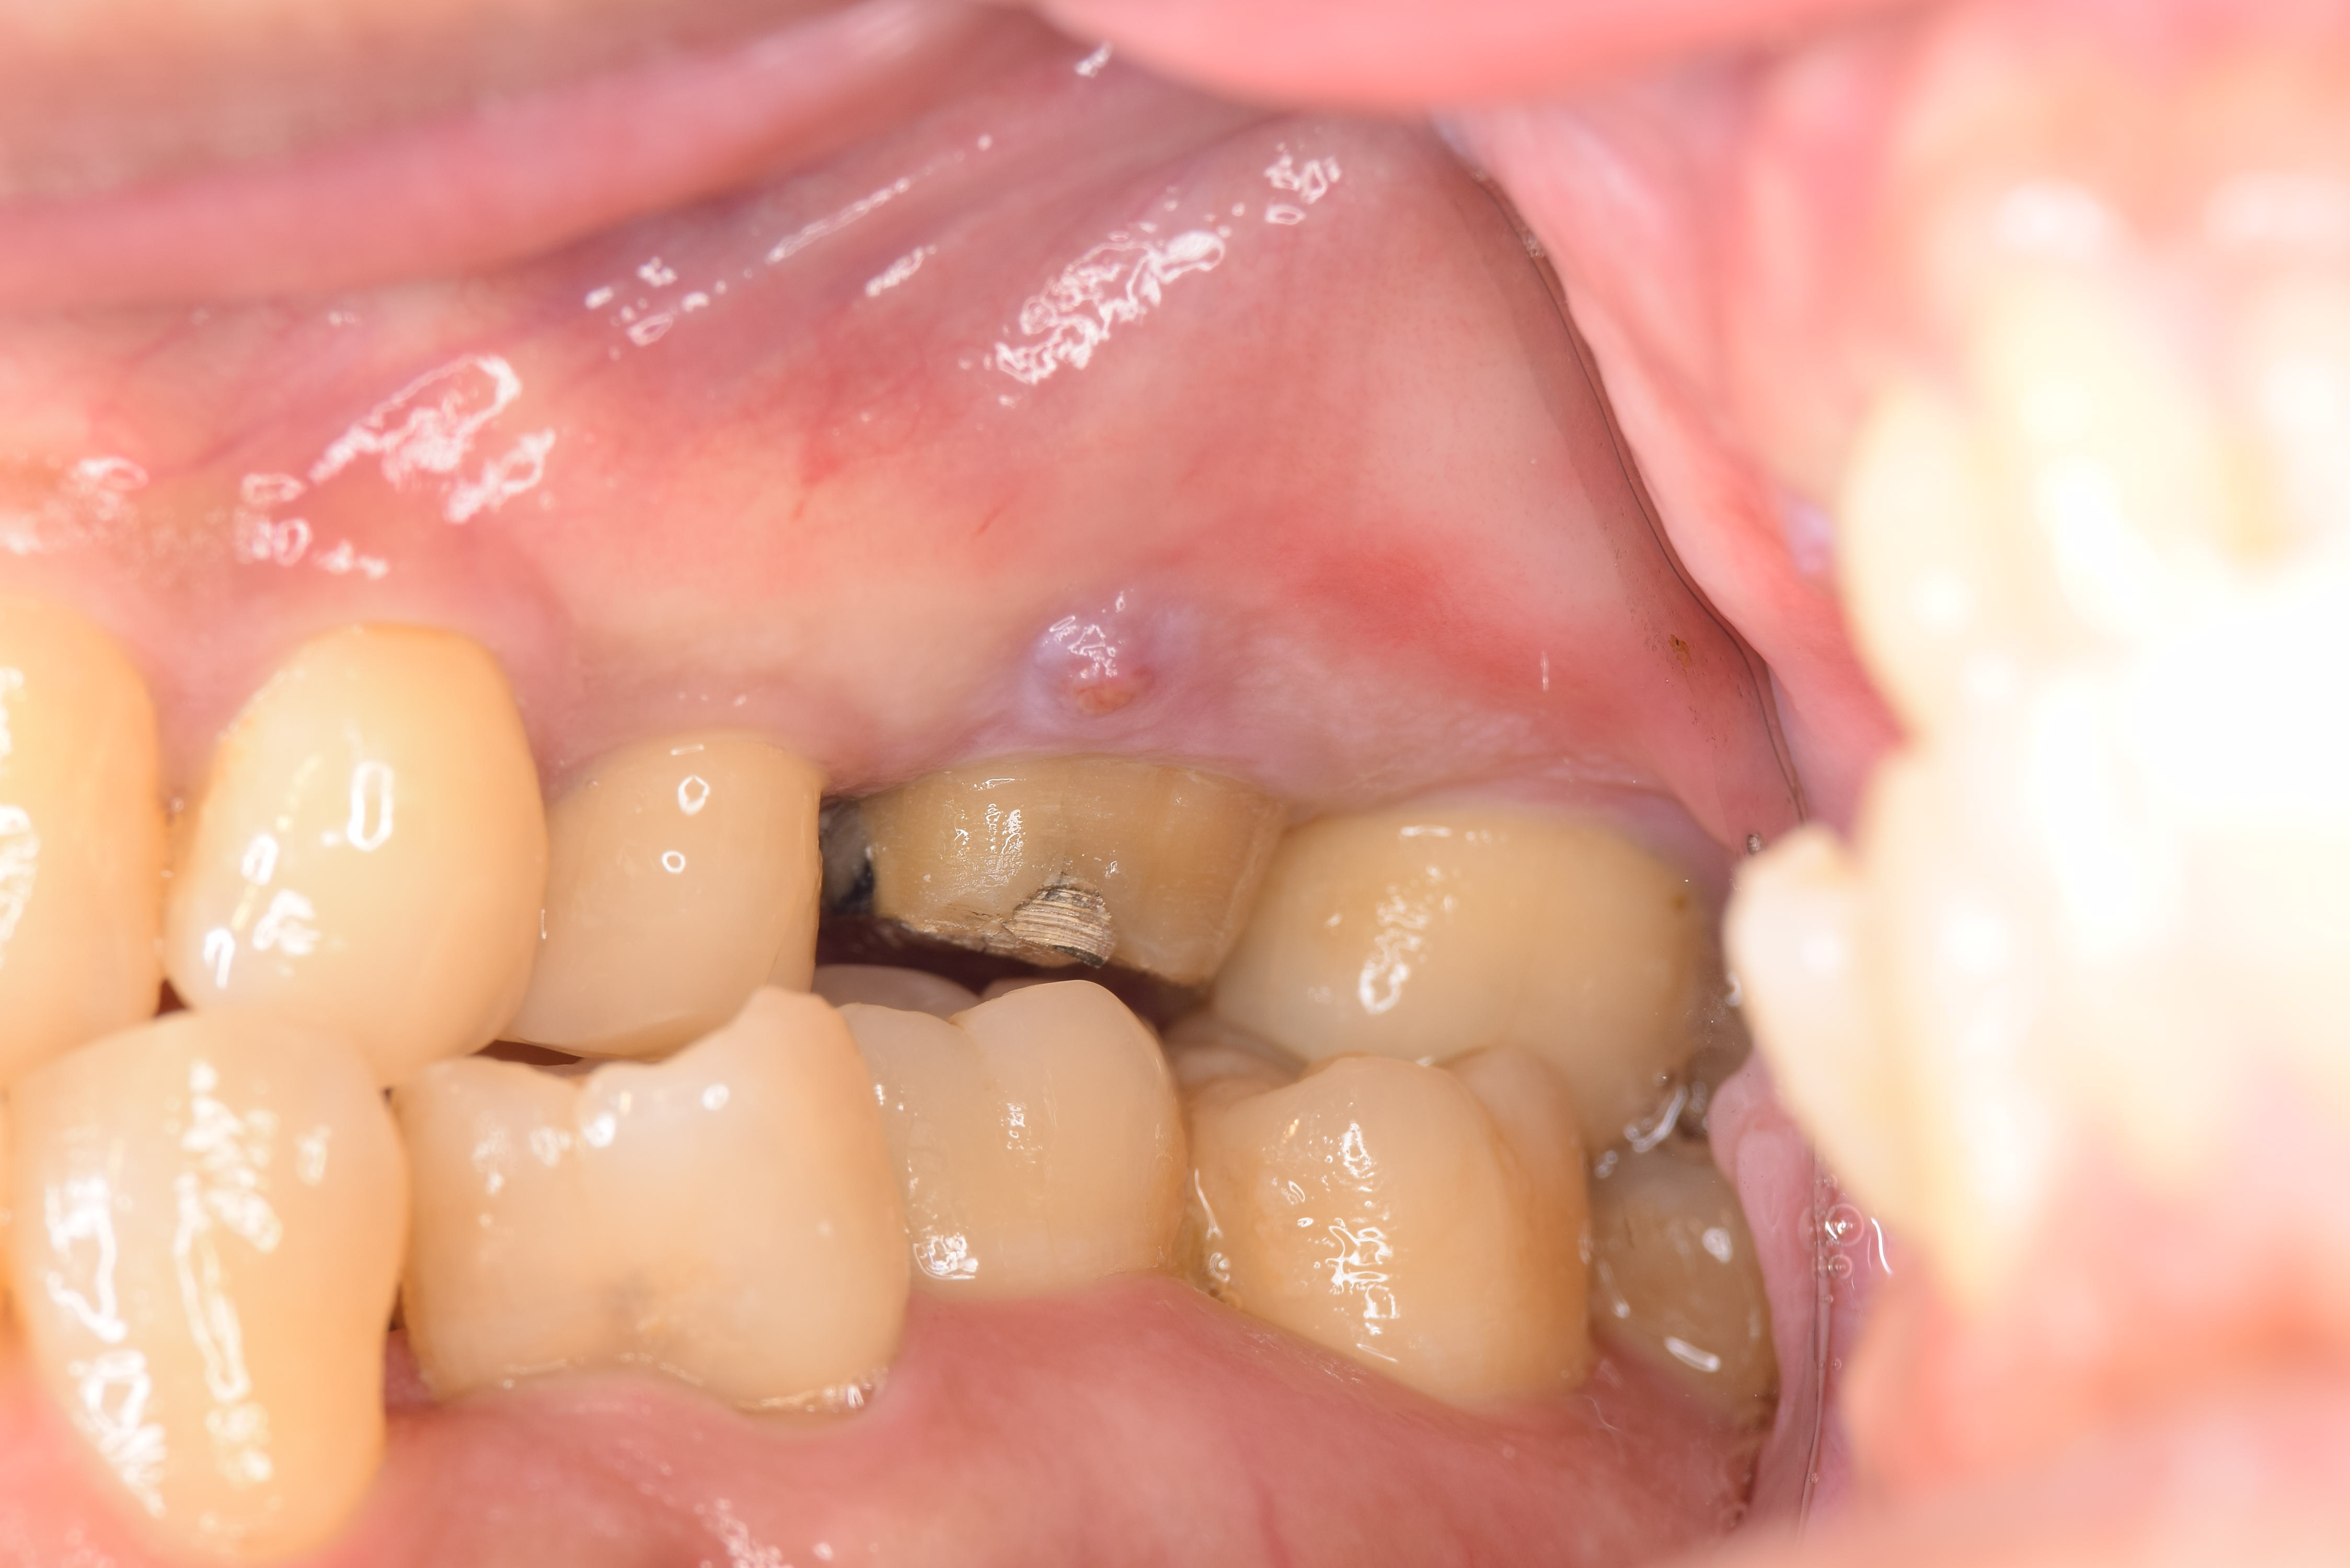

術前の状態です。小さな膿の袋があります。(ミラー像)

術後1ヶ月の状態です。

綺麗に膿の袋が消えているのがわかります。